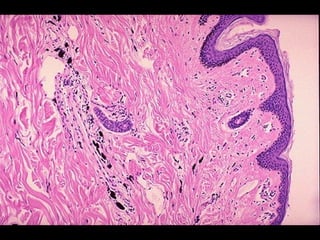

ACUMULACIÓN DE PIGMENTOS •-PIGMENTOS: sustancias coloreadas endógenas (normales o anormales) o exógenas que bajo ciertas circunstancias se acumulan intracelularmente.- •- PIGMENTOS EXÓGENOS: polvo de carbón (antracosis/neumoconiosis del trabaj ador del carbón), tatuajes. En ambos casos, la acumulación del pigmento tiene lugar en el citoplasma de los macrófagos residentes del tejido y son permanentes.-

ACUMULACIÓN DE PIGMENTOS •-PIGMENTOS ENDÓGENOS: a) lipofucsina (derivada de la peroxidación lipídica de los lípidos poli-insaturados de las membranas sub-celulares); b) melanina (catalización oxidativa de la tirosina a dihidrofenilalanina por la tirosinasa melanocítica) ; c) hemosiderina (derivado de la hemoglobina, representa agregados de micelas de ferritina; hemosiderófagos/hemosiderosis/hemocromat osis); d) bilirrubina (colestasis).-